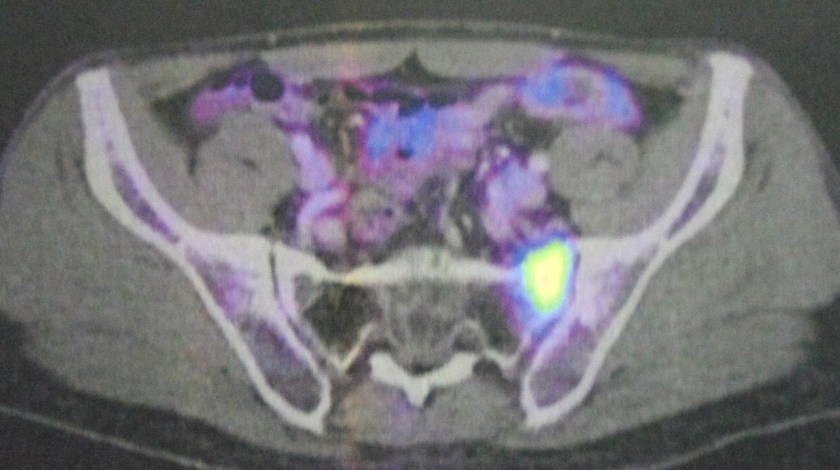

Study the three pictures below and compare them with the PET scan done on 10 August 2017 (above). You don’t need to be a doctor to know that PK is not getter better. He is getting worse and the cancer has spread more widely.

The PET scan report of 11 April 2018 stated the following:

- Mixed metabolic changes in the retroperitoneal and pelvic nodes.

- New development seen at thoracic stomach wall nodule and peri-bowel node at celiac axis, and celiac trunk nodes.